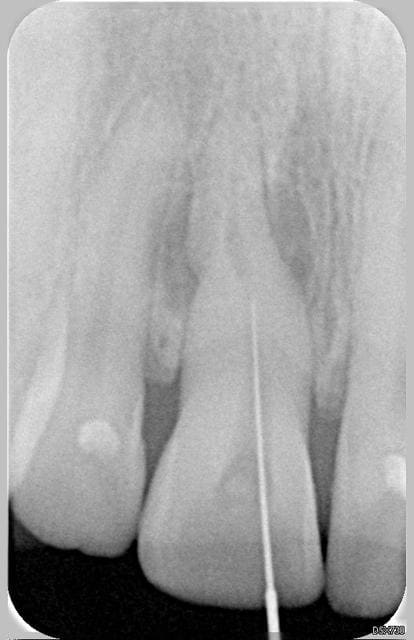

la suite le 20.11, ouverture de chambre, néttoyage de la dentine tertiaire et pose d'un EDTA.

20.11 - Eugenol